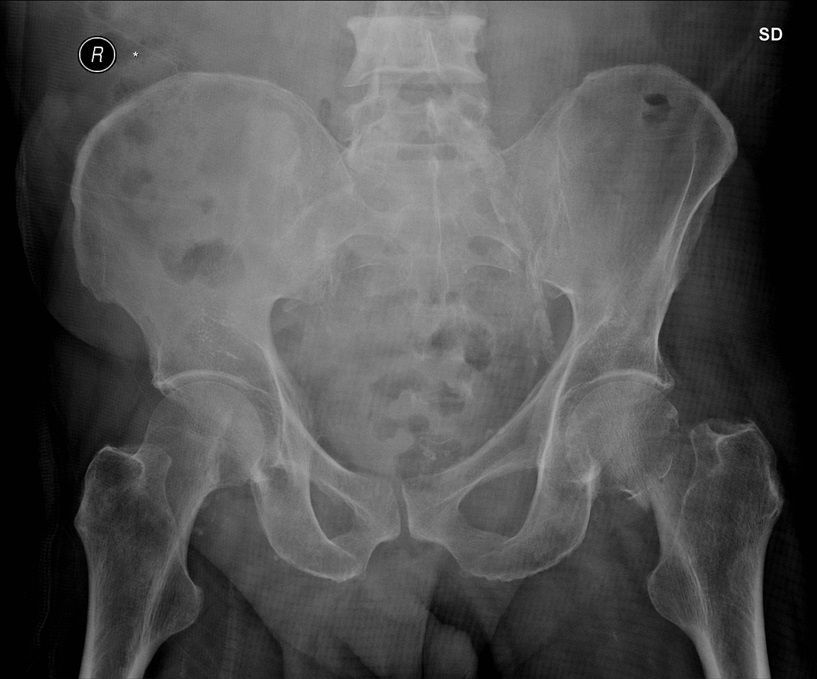

Question 4

Question

Which operation would you perform?

Answer

• THR

• Hemiarthroplasty